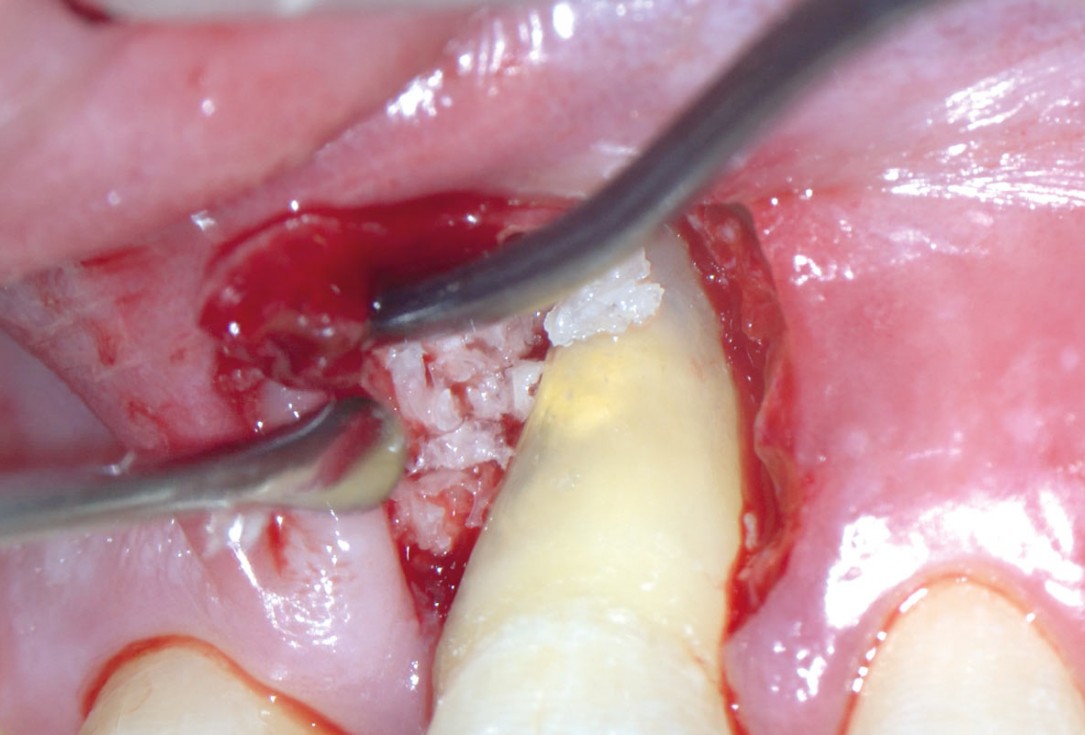

05/11 - Application of maxgraft® granules to fill the defectEntire papilla preservation technique (EPP) for the regenerative treatment of a severely compromised central incisor - Dr. S. Aslan